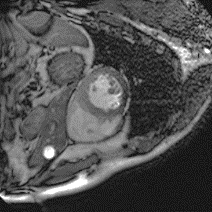

Although supervised deep-learning has achieved promising performance in medical image segmentation, many methods cannot generalize well on unseen data, limiting their real-world applicability. To address this problem, we propose a deep learning-based Bayesian framework, which jointly models image and label statistics, utilizing the domain-irrelevant contour of a medical image for segmentation. Specifically, we first decompose an image into components of contour and basis. Then, we model the expected label as a variable only related to the contour. Finally, we develop a variational Bayesian framework to infer the posterior distributions of these variables, including the contour, the basis, and the label. The framework is implemented with neural networks, thus is referred to as deep Bayesian segmentation. Results on the task of cross-sequence cardiac MRI segmentation show that our method set a new state of the art for model generalizability. Particularly, the BayeSeg model trained with LGE MRI generalized well on T2 images and outperformed other models with great margins, i.e., over 0.47 in terms of average Dice. Our code is available at https://zmiclab.github.io/projects.html.